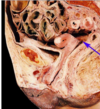

Label 1-14

A

1 Ilium

2 Rectum

3 Recto-uterine fold

4 Ovary

5 Uterine tube

6 Urinary bladder

7 Urethra

8 Labium minus

9 Recto-uterine pouch of

Douglas

10 Uterus (uterovesical

pouch)

11 Ligament of the head of

the femur

12 Head of femur

13 Vestibule of vagina

14 Labium majus